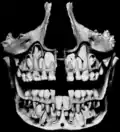

Formação dos dentes. -

Dentes decíduos, erupção dos permanentes. -

Dentes, e seio maxilar.